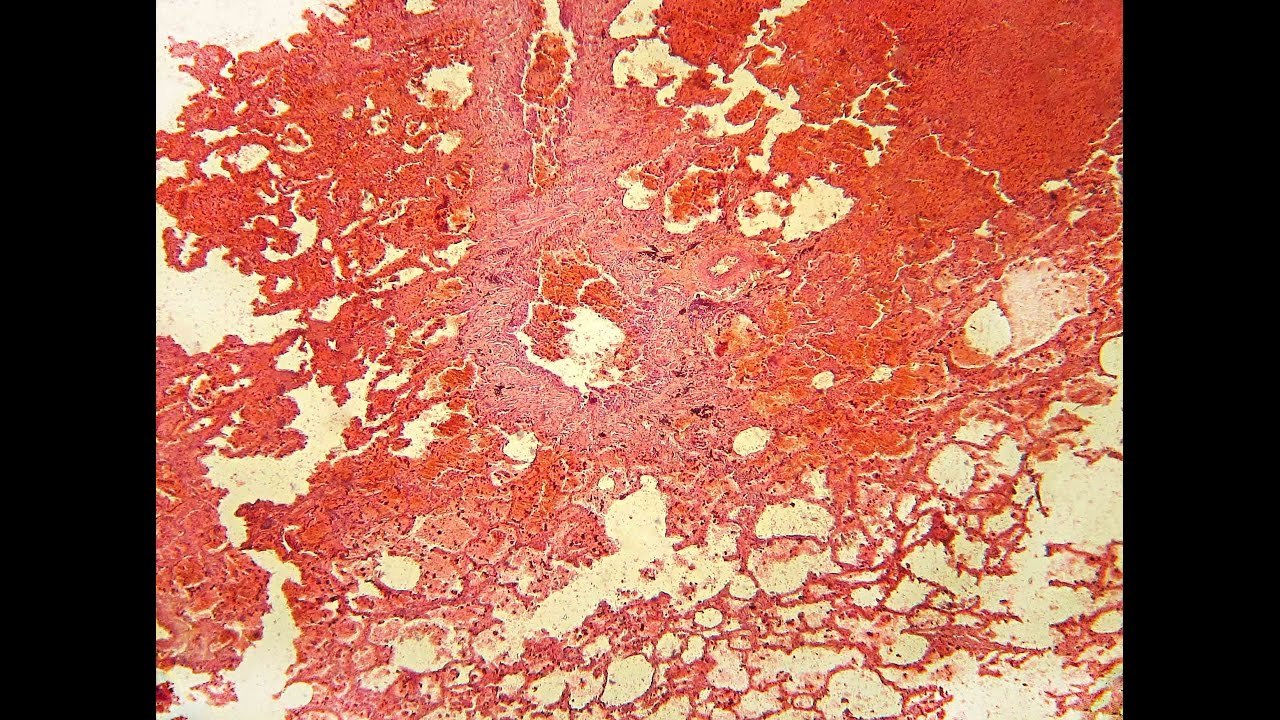

Геморрагический инфаркт легкого гематоксилин эозин

Геморрагический инфаркт легкого окраска гематоксилином

Геморрагический инфаркт легкого гистология

Геморрагический инфаркт легкого микропрепарат